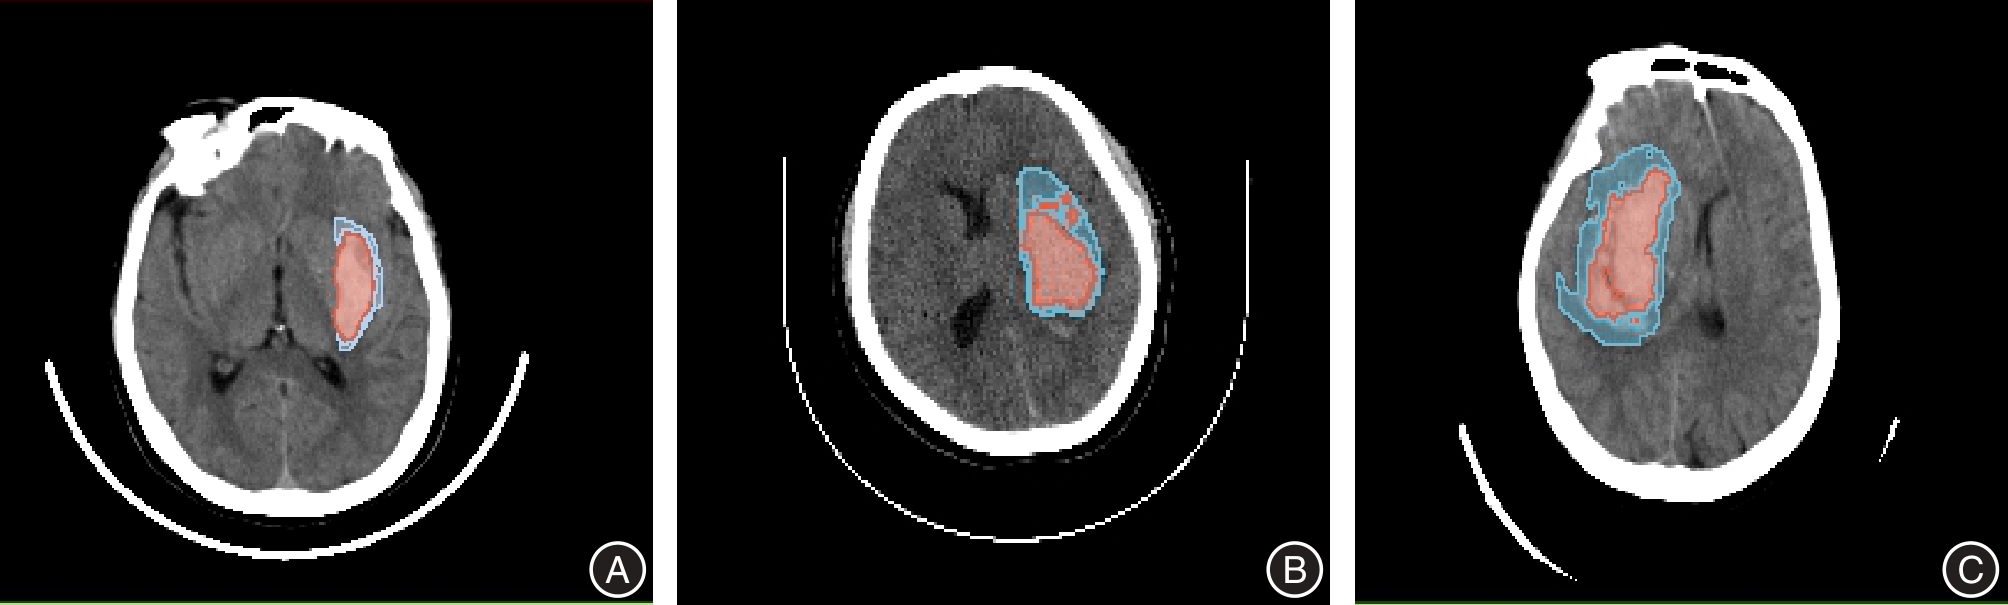

CAO L, LIU M, WANG M, et al. 3D slicer-based calculation of hematoma irregularity index for predicting hematoma expansion in intracerebral hemorrhage[J]. BMC Neurol, 2022,22(1):452. doi:10.1186/s12883-022-02983-w

doi: 10.1186/s12883-022-02983-w

LI S, WANG L. 3D Slicer-Assisted Preoperative Planning Enhances Hematoma Evacuation in Stereotactic Aspiration for Intracerebral Hemorrhage[J]. World Neurosurg, 2025,195:123684. doi:10.1016/j.wneu.2025.123684

doi: 10.1016/j.wneu.2025.123684